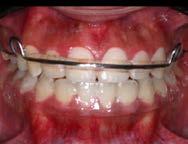

Se presenta una paciente clase ll esquelética en los estudios extrao rales en la fotografía de frente se ve hiperdivergente con una mordi da profunda de 5mm, un diastema, y refiere como motivo de consulta "no me gusta el espacio entre mis dien tes" (Figura 1).

En los estudios intraorales de inicio en las fotografías se muestra en la de frente el diastema anterior, con la línea media dental superior e inferior no coincidentes, la mordida profun da anterior (Figura 2), en la lateral derecha clase l molar y canina bila teral (Figura 3), el apiñamiento leve superior e inferior y la forma de las arcadas.

Órganos Dentarios (OD) 11-16-37, de rotación en los caninos 13-23-33, de extrusión en el premolar 45 y de control radicular en los OD 14-1524-25-34-35-43-44. Se corrigió la mordida profunda con bite ramps en alineadores del 6 al 15, se realizaron cortes de precisión en alineadores para el uso de elásticos intermaxila res en vector clase ll largos 3/16 4½ oz. (Figura 6).

En el refinamiento se planificó el detallado, se llevó a cabo con el uso de 22 alineadores superiores e infe riores previa una preparación dental, se colocaron attachments optimi zados, multiplano en OD 22- 27, de rotación en el OD 33, 35, 43, 44 de control radicular OD 23 de extrusio nes en los 34, 45, 11, 12, Power Rid ges en el 12 y 22 (Figura 7).